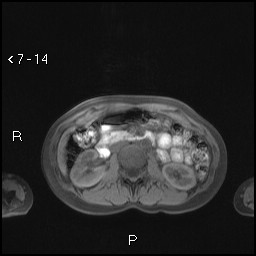

Aspetti RM: piccolo nodulo dell’istmo pancreatico ipointenso in T2.

image